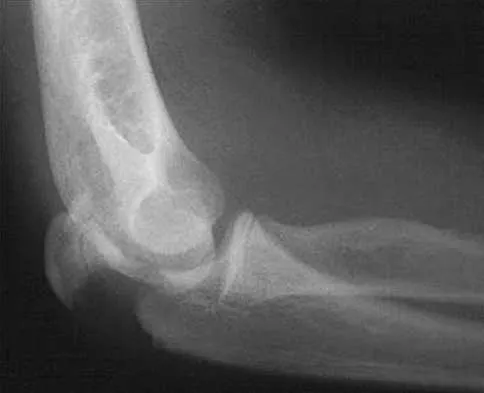

A 19-year-old man has had pain and swelling in his left forearm for the past 8 months. Laboratory studies show a mildly elevated WBC count and erythrocyte sedimentation rate. Radiographs are shown in Figures 58a and 58b, a CT scan is shown in Figure 58c, and T1- and T2-weighted MRI scans are shown in Figures 58d and 58e, respectively. A biopsy specimen is shown in Figure 58f. Immunohistochemistry demonstrates that the lesion is negative for leukocyte common antigen (CD34). What is the most common cytogenetic translocation associated with this lesion?

Explanation

The imaging studies show a permeative lytic destructive lesion in the proximal radius with "hair-on-end" periosteal reaction and a large soft-tissue mass most consistent with Ewing's sarcoma. The pathology reveals monotonous sheets of "round blue" cells. This limits the differential diagnosis to primary lymphoma of bone versus Ewing's sarcoma. These are best differentiated by immunohistochemistry, cytogenetics, and flow cytometry. Lymphoma of bone is typically CD34 positive and CD99 negative; whereas, the reverse is true of Ewing's sarcoma, CD34 negative and CD99 positive. The most common cytogenetic translocation with Ewing's sarcoma is 11; 22; 21; 22 and 7; 22 translocations have also been reported in Ewing's sarcomas. The X; 18 translocation is most commonly associated with synovial cell sarcomas; the 12; 22 translocation is most commonly associated with clear cell sarcomas; the 2; 13 translocation is most commonly associated with alveolar rhabdomyosarcomas, and the 12; 16 translocation is most commonly associated with myxoid liposarcomas. Flow cytometry is used to characterize the cell types of lymphomas. Womer R: The cellular biology of bone tumors. Clin Orthop Relat Res 1991;262:12-21. Yamaguchi U, Hasegawa T, Morimoto Y, et al: A practical approach to the clinical diagnosis of Ewing's sarcoma/primitive neuroectodermal tumour and other small round cell tumours sharing EWS rearrangement using new fluorescence in situ hybridisation probes for EWSR1 on formalin fixed, paraffin wax embedded tissue. J Clin Pathol 2005;58:1051-1056.